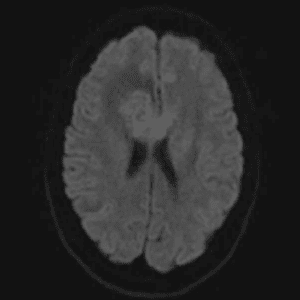

Case #42

Giant cerebral aneurysm